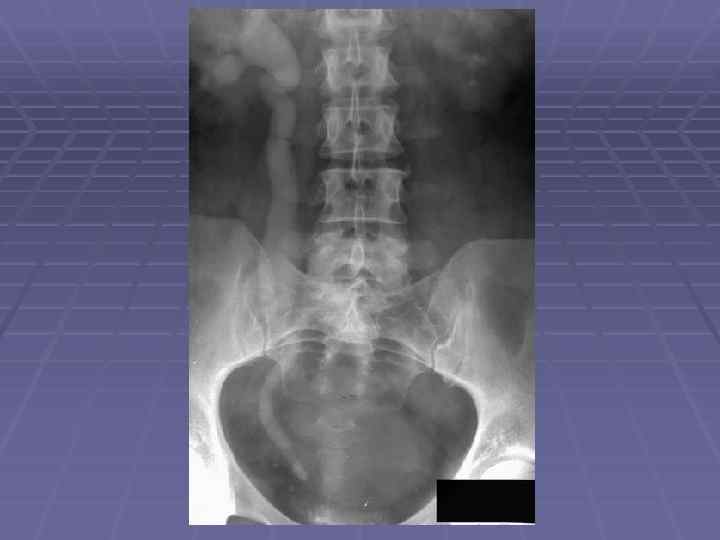

На рентгенограмме верхняя граница почки обычно располагается на уровне XI грудного позвонка, нижняя — на уровне III поясничного позвонка. Верхний полюс почки достигает XI ребра, а нижний расположена на 3— 5 см выше гребешка подвздошной кости. Тень левой почки обычно расположена выше правой на 1 -2 см и делится XII ребром пополам, в то время как тень правой пересекается XII ребром на границе верхней и средней третей.

МОЧЕТОЧНИКИ Мочеточник имеет длину 25— 30 см. Просвет его в норме не одинаков на всем протяжении. От лоханки, мочеточник отходит медиально и с легким изгибом идет вдоль m. psoas, а затем более или менее параллельно и почти вплотную к позвоночнику до lin. innominata. Здесь он перекрещивается с подвздошными сосудами и далее располагается по внутренней стенке малого таза, делая небольшой изгиб в латеральную сторону. Затем мочеточник направляется медиально ко дну мочевого пузыря, в который впадает почти под прямым углом. Каждый мочеточник имеет три физиологических сужения: § у места перехода лоханки в мочеточник; § у места перекреста с подвздошными сосудами на lin. innominata; § в месте впадения мочеточника в мочевой пузырь.

МОЧЕВОЙ ПУЗЫРЬ § Формы и размеры мочевого пузыря на цистограмме могут быть весьма разнообразны и в основном зависят от пола и возраста. Нормальный мочевой пузырь обычно имеет округлую, продолговатую или пирамидальную форму; нижняя граница его расположена на уровне верхнего края лобкового сочленения или несколько ниже его, верхняя достигает уровня III крестцового позвонка. § У детей на цистограмме тень мочевого пузыря несколько приподнята над лонным сочленением, имеет грушевидную форму и суженной своей частью направлена вниз. У женщин поперечный диаметр мочевого пузыря обычно больше продольного